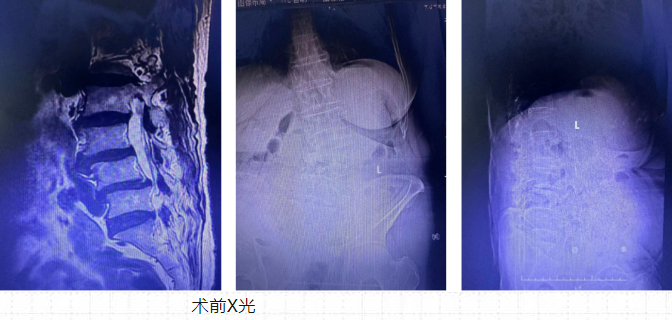

王清富博士帶領團隊仔細研究了李婆婆的腰椎CT、MRI平掃片,初步診斷為:腰椎退變性疾病,腰椎側彎旋轉畸形,合并腰椎管狹窄,L3、L4椎體向前滑脫,L3/4間盤突出,L4/5椎間盤膨出嚴重壓迫神經。最終,骨外科團隊擬定采取脊柱微創(chuàng)手術方式減壓+微創(chuàng)新技術(斜外側腰椎融合術)來解決李婆婆因腰椎神根經壓迫引起的左下肢疼痛和麻木問題。